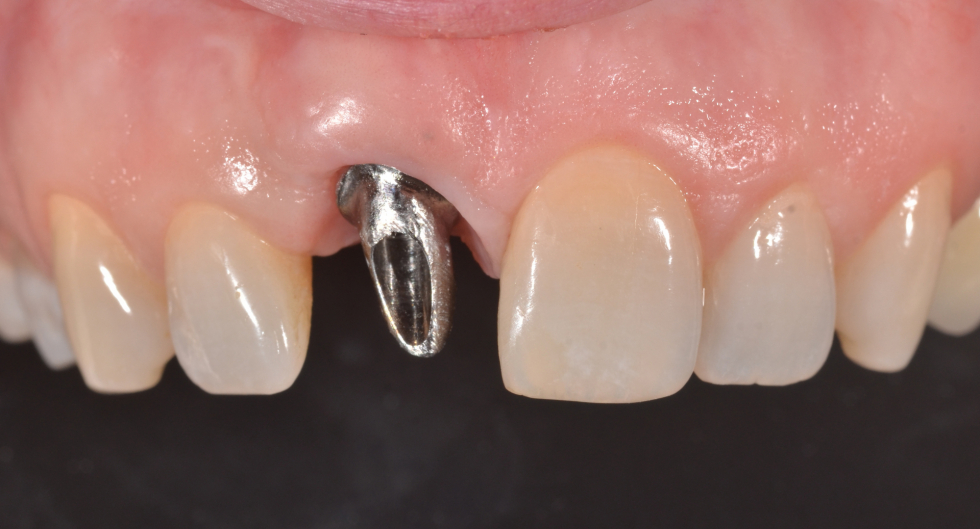

miglioramento estetico di un dente su impianto

un caso emblematico dove un impianto sostituisce la perdita di un dente. Qui l'intervento di innesto gengivale e una dente di forma e colore sbagliati hanno creato un inestetismo che impedisce alla paziente di sorridere

evidente anomalia della forma del dente e la tumefazione della gengiva dovuta ad un intervento di chirurgia

modificando la forma del dente con il provvisorio si ottiene già un primo rimodellamento della gengiva

il moncone avvitato sull'impianto